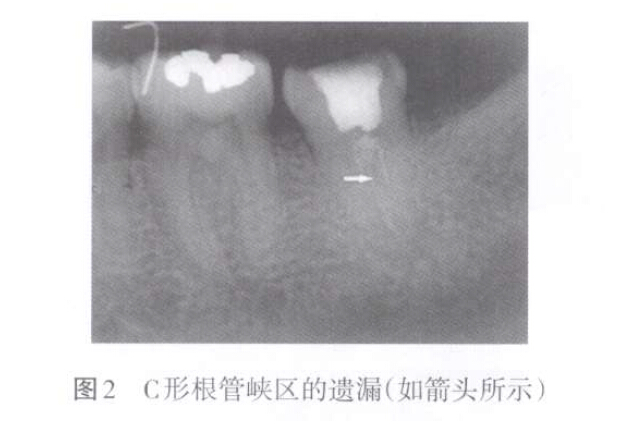

1. 2 側(cè)副根管遺漏

側(cè)副根管主要是指根管側(cè)支、根尖分歧、副根管、管間交通、峽區(qū)等根管變異。側(cè)副根管遺漏表現(xiàn)為上述區(qū)域未能有效預(yù)備和充填(圖2)